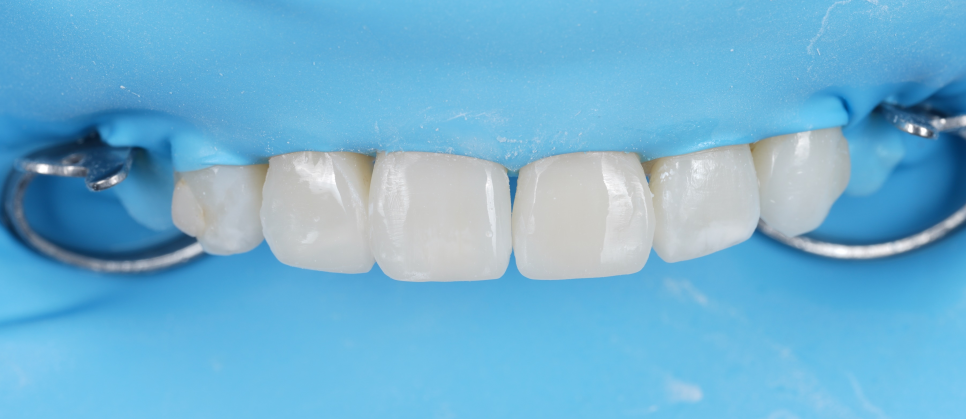

그리고 #12^13 사이에 교정 후 흔히 볼 수 있는

블랙 트라이앵글(잇몸이 꺼지면서 생기는 틈)이

생겼더라고요.

그것도 메워드리기로 했고요.

투명 교정 시에는

'어태치먼트(Attachments-부착물)'

라는 것을 붙여서 치아를 움직이는데요.

하방으로 반점치가 있더라고요.

반점치도 레진으로 해결하기로 했습니다.

치료 계획

#11,21 길이 연장

#12 블랙 트라이앵글 메우기

#12,22 반점치 제거

이렇게 계획을 세웠습니다.

촬영일 : 250714

아래 앞니는 전체적으로 교모(씹으면서 생긴

닳은 것)이 심했는데 일단 위 앞니를 먼저

해결하기를 원하셔서 지켜보기로 했습니다.